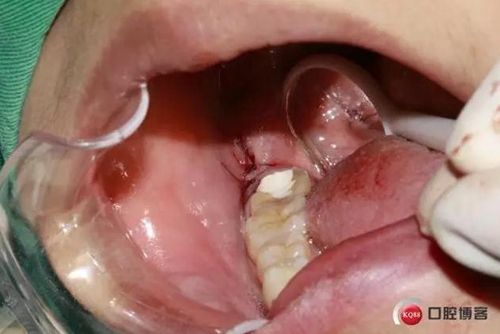

下面CBCT,可以看到兩個牙根的根尖三分之一在神經(jīng)管里面。

下面?zhèn)惹忻?/p>

1500632972_273609.jpg

CBCT神經(jīng)管標(biāo)線,可以看到標(biāo)線不能連續(xù),中間被阻斷。